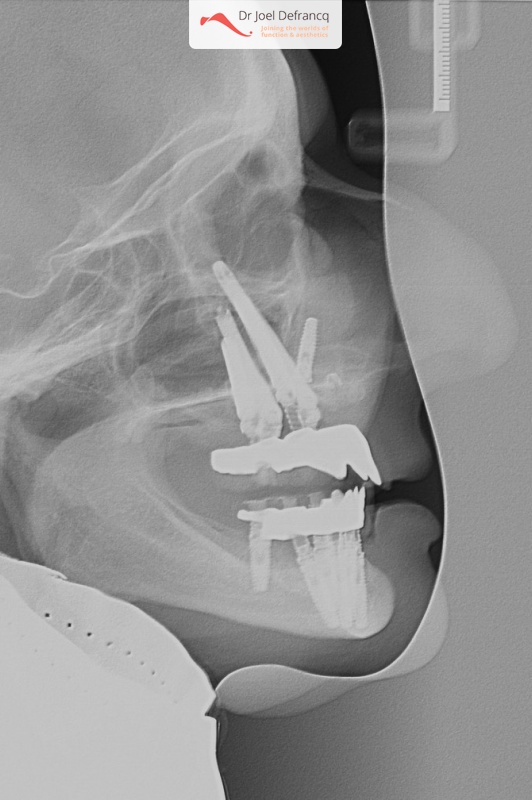

Kait: new teeth in a week - 4 zygoma implants

Diagnose van het gezicht

- Te kort gezicht

- Te lange bovenkaak

- Klasse II divisie 1

Behandeling tandheelkundige implantaten

- Zygoma implantaten